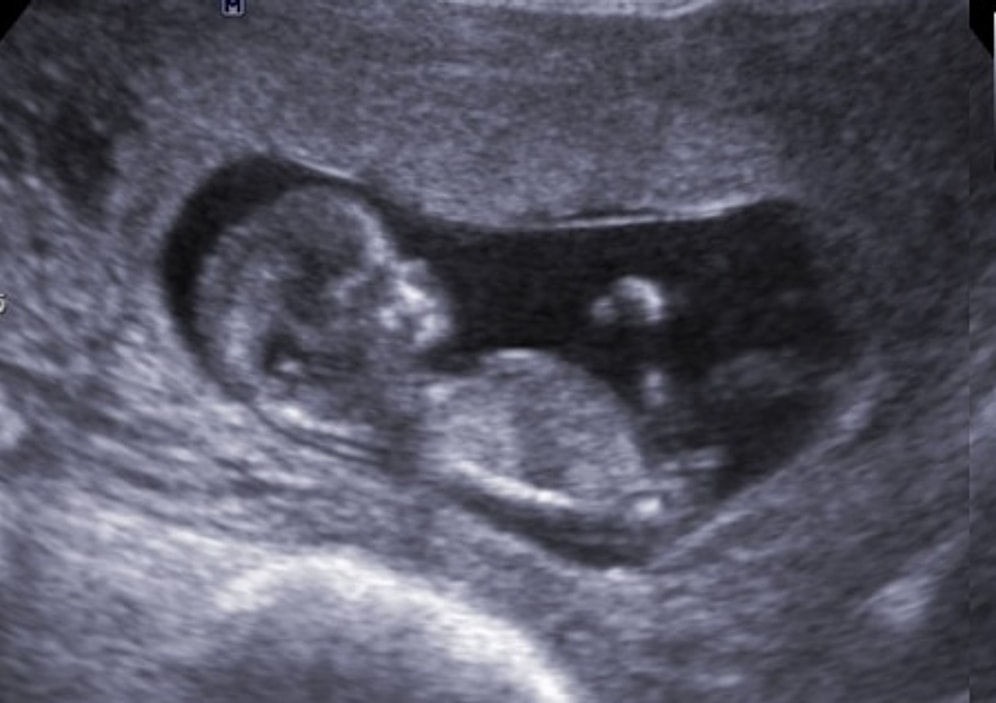

Hamilelikte 11. Hafta: Artık Göbeğiniz Belirginleşiyor!

Bebeğinizin boyu yaklaşık olarak 4 ile 6 cm, kilosu ise 8 ile 10 gr. civarına gelmiştir. Gebelikte 11.hafta, bebeğinizin hızlı bir şekilde gelişim gösterdiği haftalardan biridir. Organları tamamlanmış sayılır. Baş ve vücut arasındaki değişim oranı bu hafta ile beraber normal değerlere gelecektir.